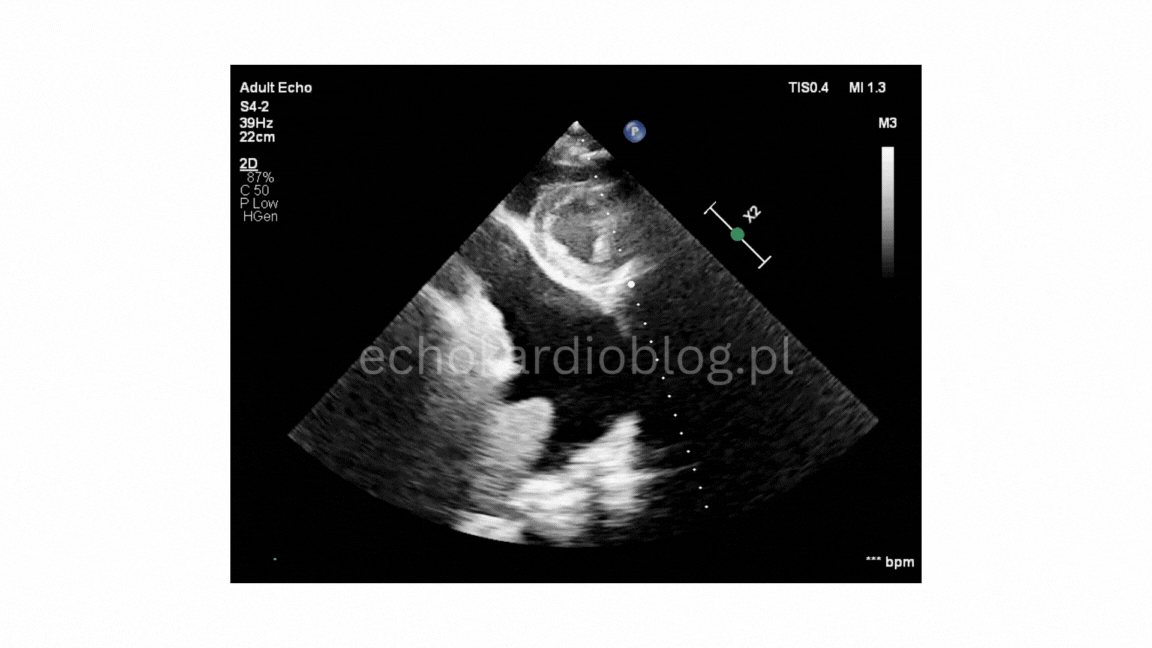

Prezentuję dwa przypadki pseudodyskinezy u pacjentów z marskością wątroby z wodobrzuszem:

przypadek 2, gdzie jest mniej nasilona postać pseudodyskinezy

We present two cases of pseudodyskinesia in patents with liver cirrhosis and ascites:

Case 2- a less pronounced form of the są me phenomenon.